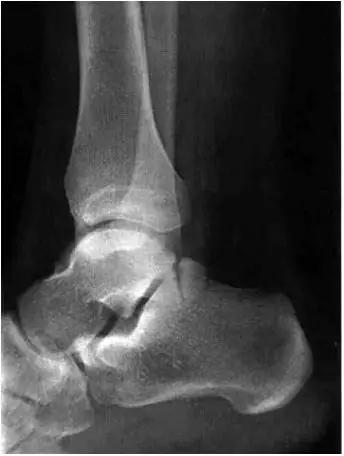

男,11岁,自述后踝下方疼痛,活动时为甚,并有一突起。

2、影像学表现:

- 踝关节正侧位X 线平片,侧位片均显示距骨后方有三角形或椭圆形的距后三角骨。部分病例伴有轻度的踝关节骨性关节病。

- MRI 检查示距后三角骨及周围软组织有水肿信号,距后三角骨和距骨之间正常的低信号纤维连接中断,出现液性信号。